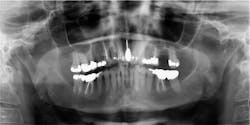

Patient: 14-year-old male

- Patient referred to oral and maxillofacial surgeon to evaluate lower third molars

- Significant, well-circumscribed, expansile radiolucencies around impacted teeth

- Medical history of mental delay

- Recent excision of a basal cell carcinoma from the patient’s chest